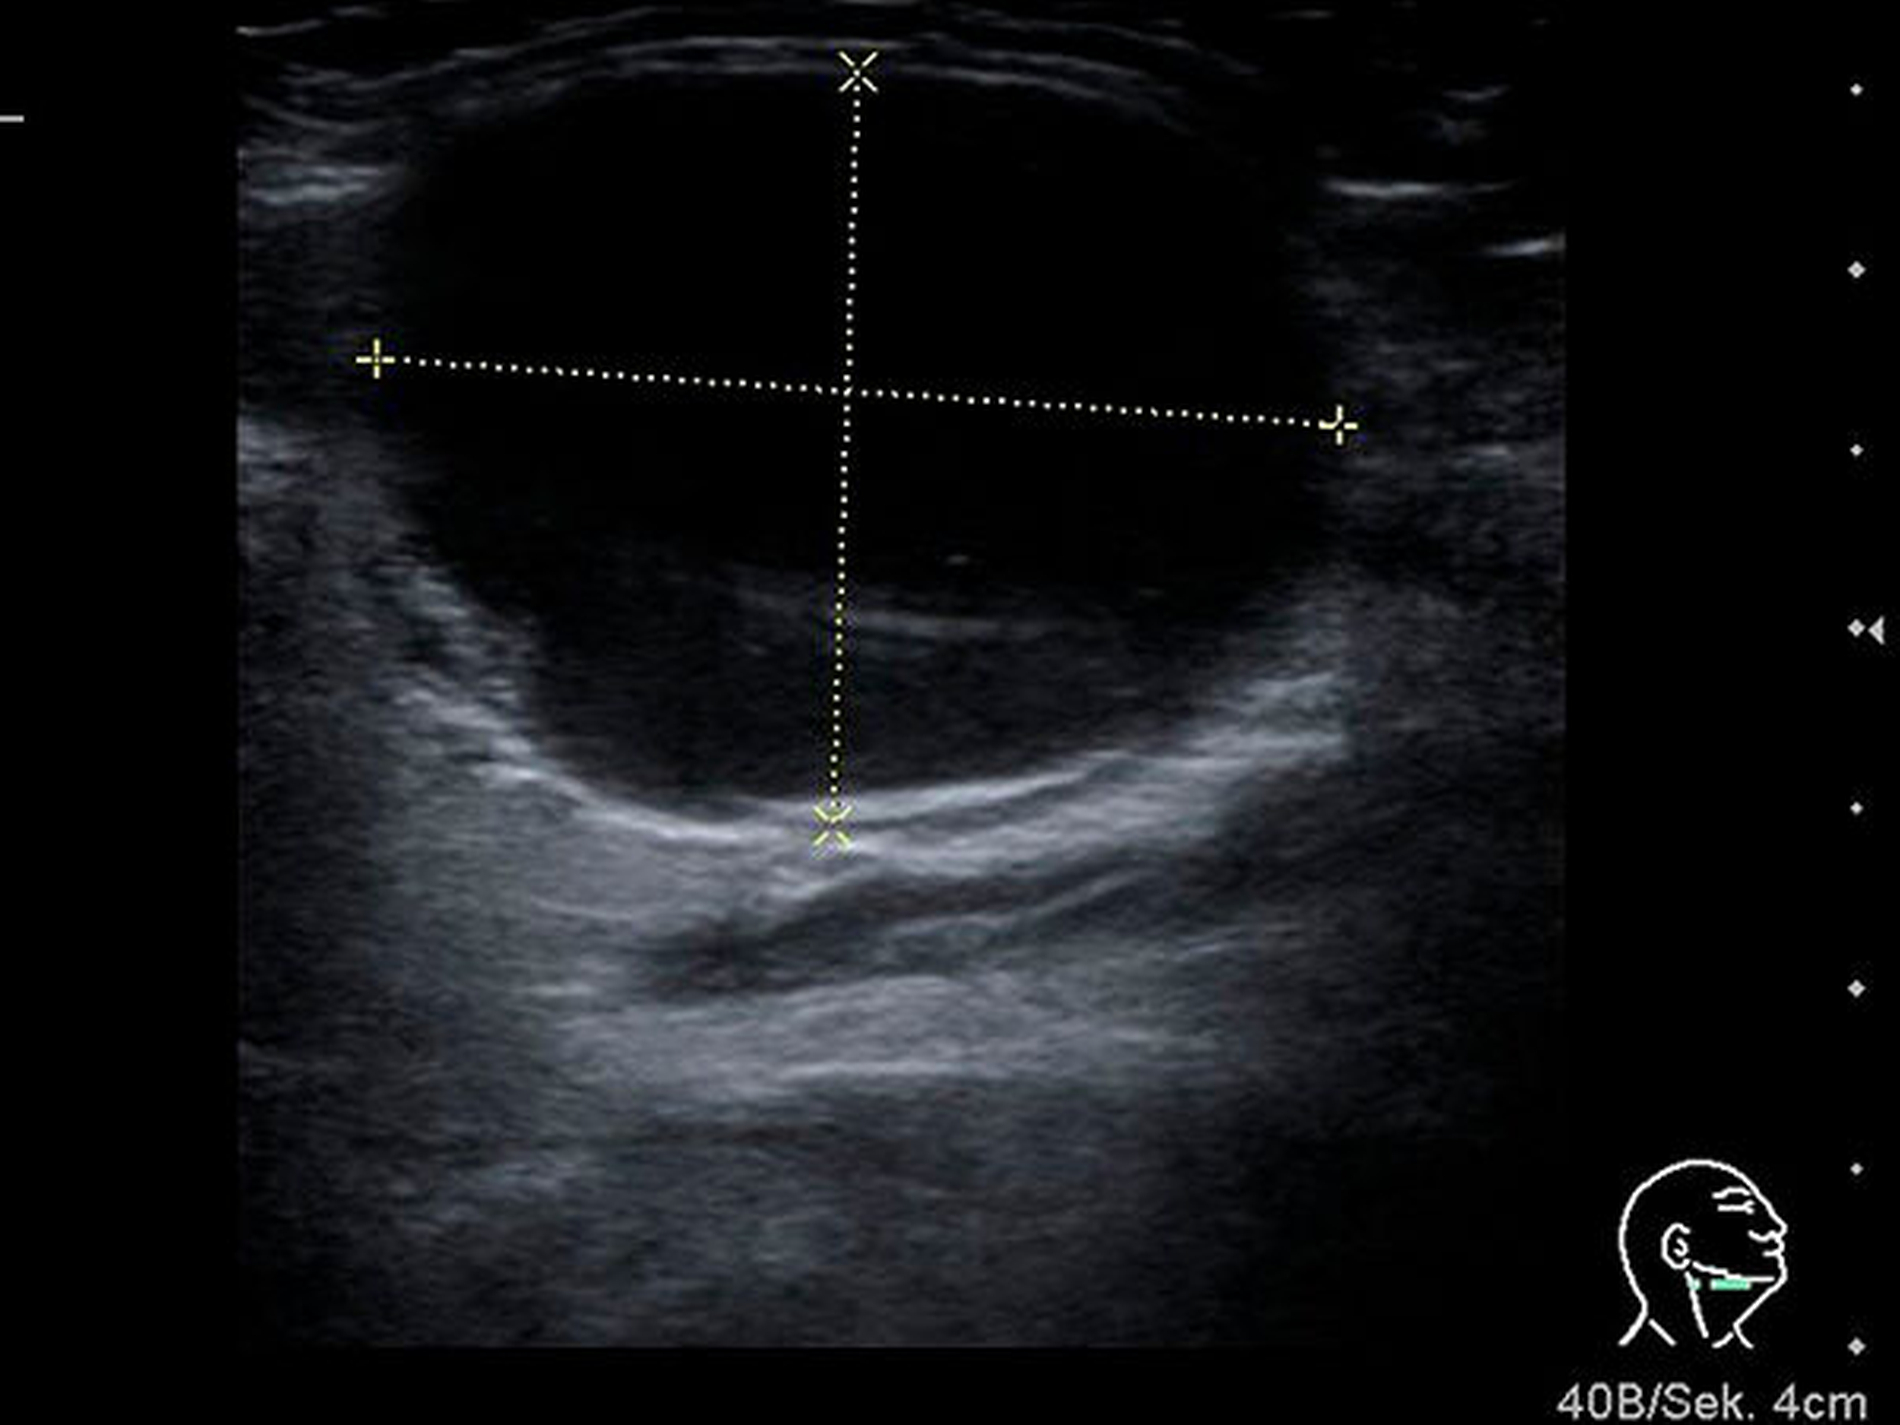

Bei der extraoralen Untersuchung fand sich eine ausgedehnte raumfordernde Schwellung cervical rechts bis nach supraklavikulär und nuchal reichend (Abbildung 1a). Diese war derb, nicht verschieblich, nicht druckdolent und nicht fluktuierend und zeigte sich auch in der Sonografie malignomsuspekt (Abbildung 1b).